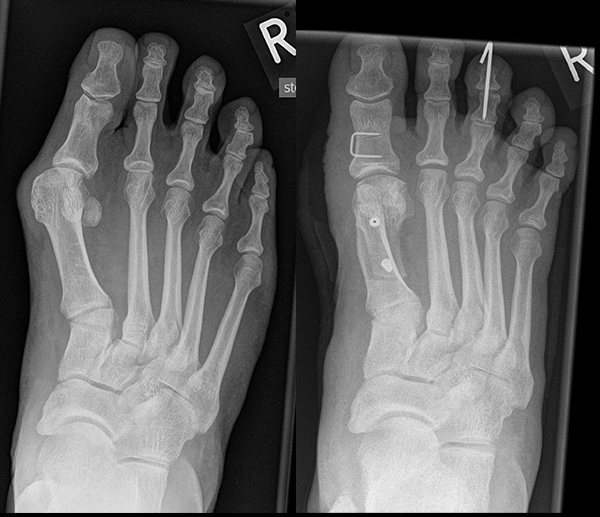

An erster Stelle der bildgebenden Diagnostik steht die konventionelle Röntgendiagnostik. Der betroffene Fuß wird dabei unter Belastung in 3 Ebenen dargestellt. Beurteilt werden der Intermetatarsale-I-Winkel (IM-Winkel), der Hallux valgus Winkel (HV-Winkel), die Lage der Sesambeine, der Arthrosegrad im MTP I Gelenk und ein mögliches plantares Klaffen „gapping“ im Tarsometatarsale-I Gelenk als Hinweis auf eine Gelenkinstabilität. Neben der reinen Beurteilung des Hallux valgus sollten immer auch die Kleinzehen beurteilt werden.

Zum Lesen der Bildbeschreibung und zur Vollansicht bitte das Bild anklicken. Bild: Markus Walther.